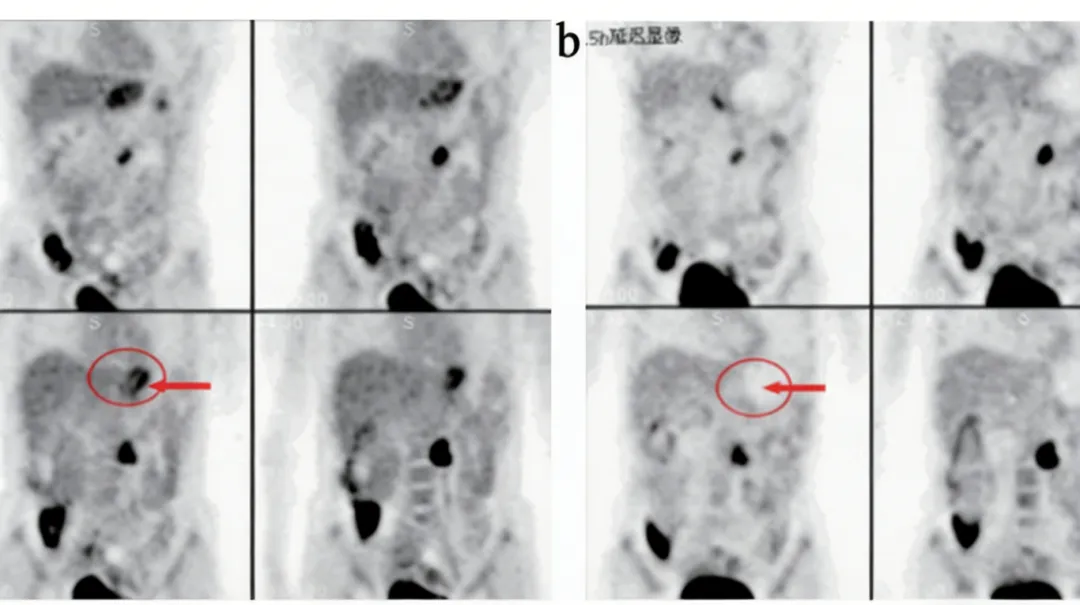

42岁女性,两肺间质性改变伴结节,肺门、纵隔淋巴结对称性肿大,FDG代谢明显增高,淋巴结穿刺病理证实结节病。

(病例来源:上海交通大学附属同仁医院核医学)

这说明,代谢高并不等于癌细胞扩散。